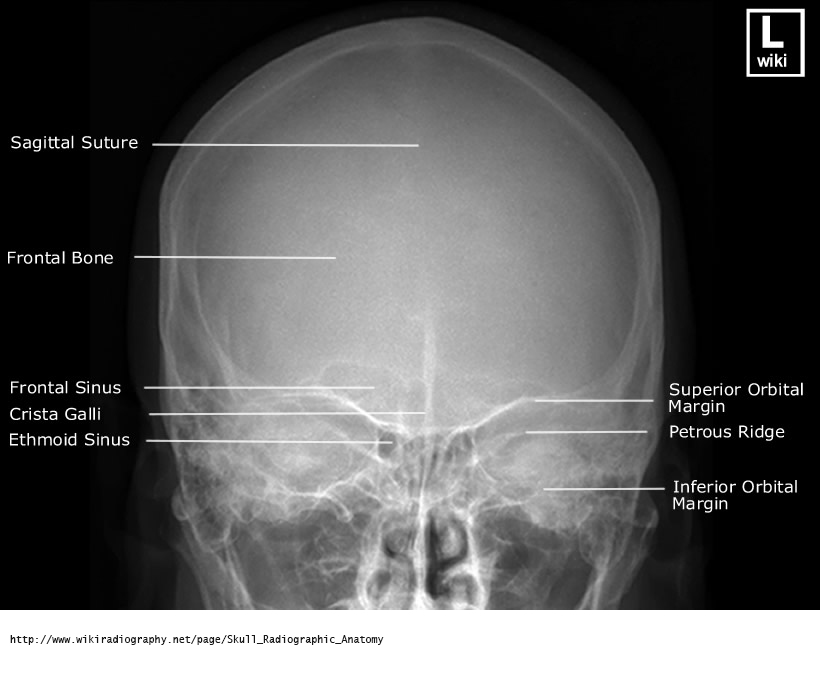

Critique - PA Skull

F/E, OML Alignment

MAIN: petrous ridges are at supraorbital rim level and fill the orbits

anterior clinoid and dorsum sellae are superior to the ethmoid air cells